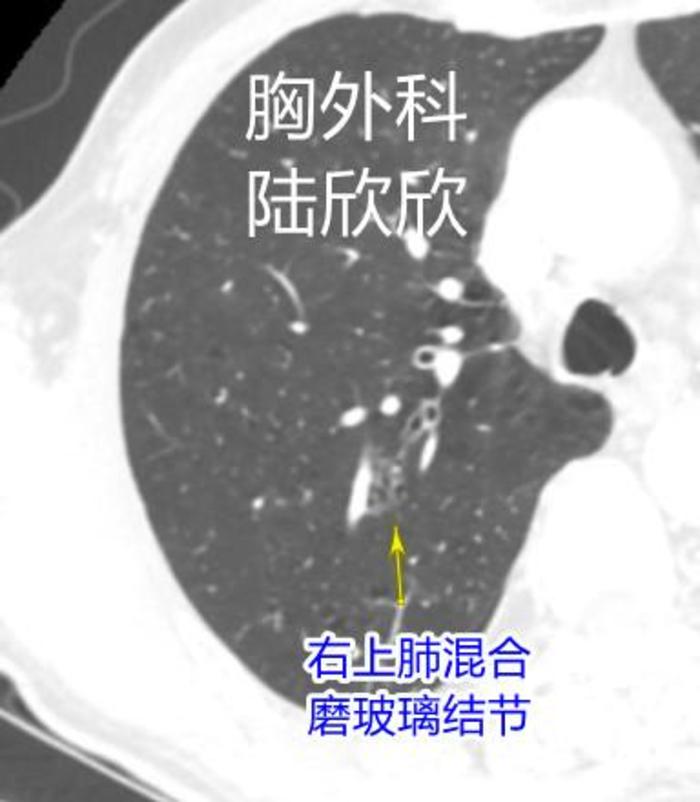

2019年6月份的一天,一个本院同事介绍一个72岁老人到我这儿看病,说是右上肺有一个磨玻璃结节。我仔细看了看CT,右上肺确实有一个磨玻璃结节。如下图。

黄色箭头上方是一个磨玻璃结节。磨玻璃结节左侧有一根静脉。这个磨玻璃结节是一个混合磨玻璃结节,大小约14×8毫米。磨玻璃结节内部结构我们可以看成两根并排放置的铁轨上放置多个球状物。这个磨玻璃结节起码微小浸润性腺癌以上阶段。